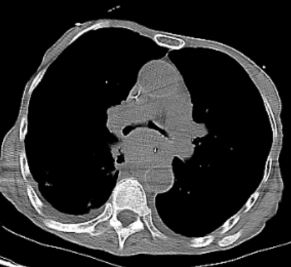

患者,81岁,因“胸闷、气喘4月,加重1天”急诊入院,入院时已因呼吸衰竭行气管插管呼吸机支持,病情凶险,患者既往确诊食管癌,近期复查提示疾病进展,已出现广泛肺转移、纵膈淋巴结重度肿大,进一步影像学及支气管镜检查证实,纵膈淋巴结肿大、肺转移病灶,病变已严重侵犯气管、隆突和左右主支气管,导致左右主支气管均出现重度狭窄,气道通畅度不足,随时可能因气道梗阻窒息死亡,且患者高龄、体质虚弱,给诊疗带来极大挑战。

2026年3月31日下午3时,在费卫东等麻醉团队密切配合下,先对患者进行全麻、肌松,呼吸介入专家俞小卫带领下,黄燕华、陈意、刘志光主任紧密配合,利用STOZE 成像系统引导,成功插入硬质气管镜鞘管,在高频通气保驾下,置入导丝,沿导丝插Y形支架到位后逐步释放支架,支架到位,最后采用球囊对支架进行扩张塑形,支架贴壁良好。